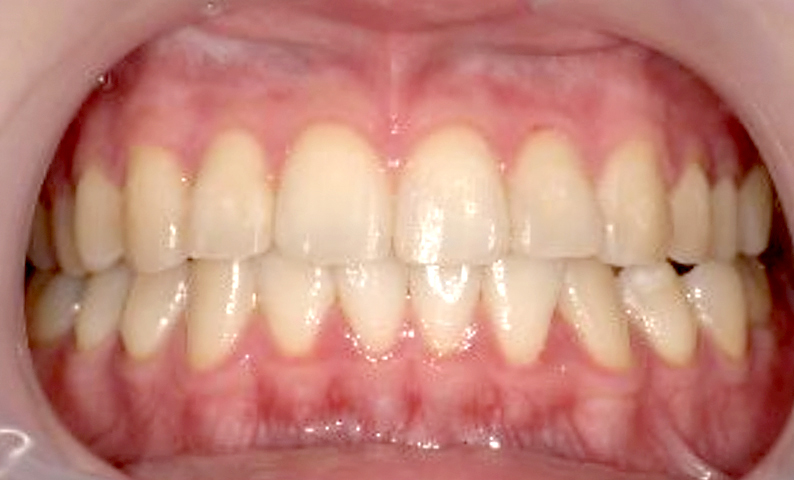

症例_002 前歯「捻転歯」症例

治療期間:7ヶ月金額:27万円+税20代女性少しのねじれ上の前歯だけ

| Before | After |